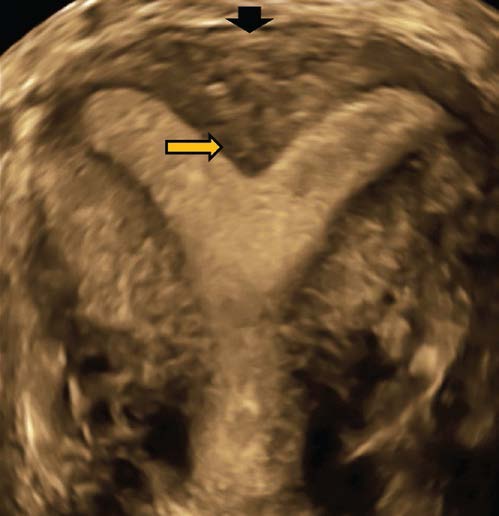

4)Histeroskopik Septum Rezeksiyonu

Rahim içi boşluğu ikiye bölen, perde olarak da adlandırılan doğuştan bir rahim bozukluğudur. Bu perde kısa olabildiği gibi bütün rahim iç tabakası boyunca rahimağzına kadar uzanabilir ve hatta rahimağzını ve vajenide ikiye bölerek vajen ağzına kadar uzanır. Rahimdeki bu perde kavitenin hacmini azalttığı için gebelik oluşumunu engelleyebilir. Gebe kalabilen hastalarda ise düşük ve erken doğum olasılığı yüksektir. Ancak bunların bir kısmı asemptomatiktir ve normal zamanında doğum yapabilir. Bu nedenle daha önce kısırlık öyküsü olmayan veya düşük yapmamış hastalarda septumun alınıp alınmaması tartışmalıdır. Çünkü septumun küçük olduğu olgularda hastaya bir zarar vermediği için tedavisi de gerekmeyebilir. Ancak düşük veya erken doğum öyküsü olan, gebe kalamayan ve tüp bebek uygulanacak hastalarda histeroskopik septum rezeksiyonu yapılmasıgerekir. Ayrıca bu septumlar adet dışı kanama ve adet sırasında şiddetli ağrıda (dismenore) yapabilir. Bu şikayetlerin varlığında da gebelik problemi veya isteği olmasa bile rezeksiyon yapılması gerekir. Ayrıca bu uterin anomalilerin varlığında üriner sistemde de doğumsal anomalilerin olabileceği akılda tutulmalıdır.